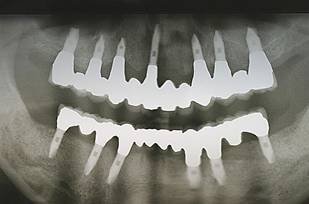

歯周病で抜歯せざるを得ず、インプラントを希望されたケース(使用インプラントはスプライン)

術前。すべての歯が歯周病の末期状態でブリッジ全体がうごいて噛めないとの訴え。右上の犬歯が腫れていました

固定式のブリッジが入っていましたが歯周病で動いています

下顎前歯部には歯石の沈着がみられます

術前パノラマレントゲン写真。根の周りが黒くなり、骨がなくなっていることがわかります